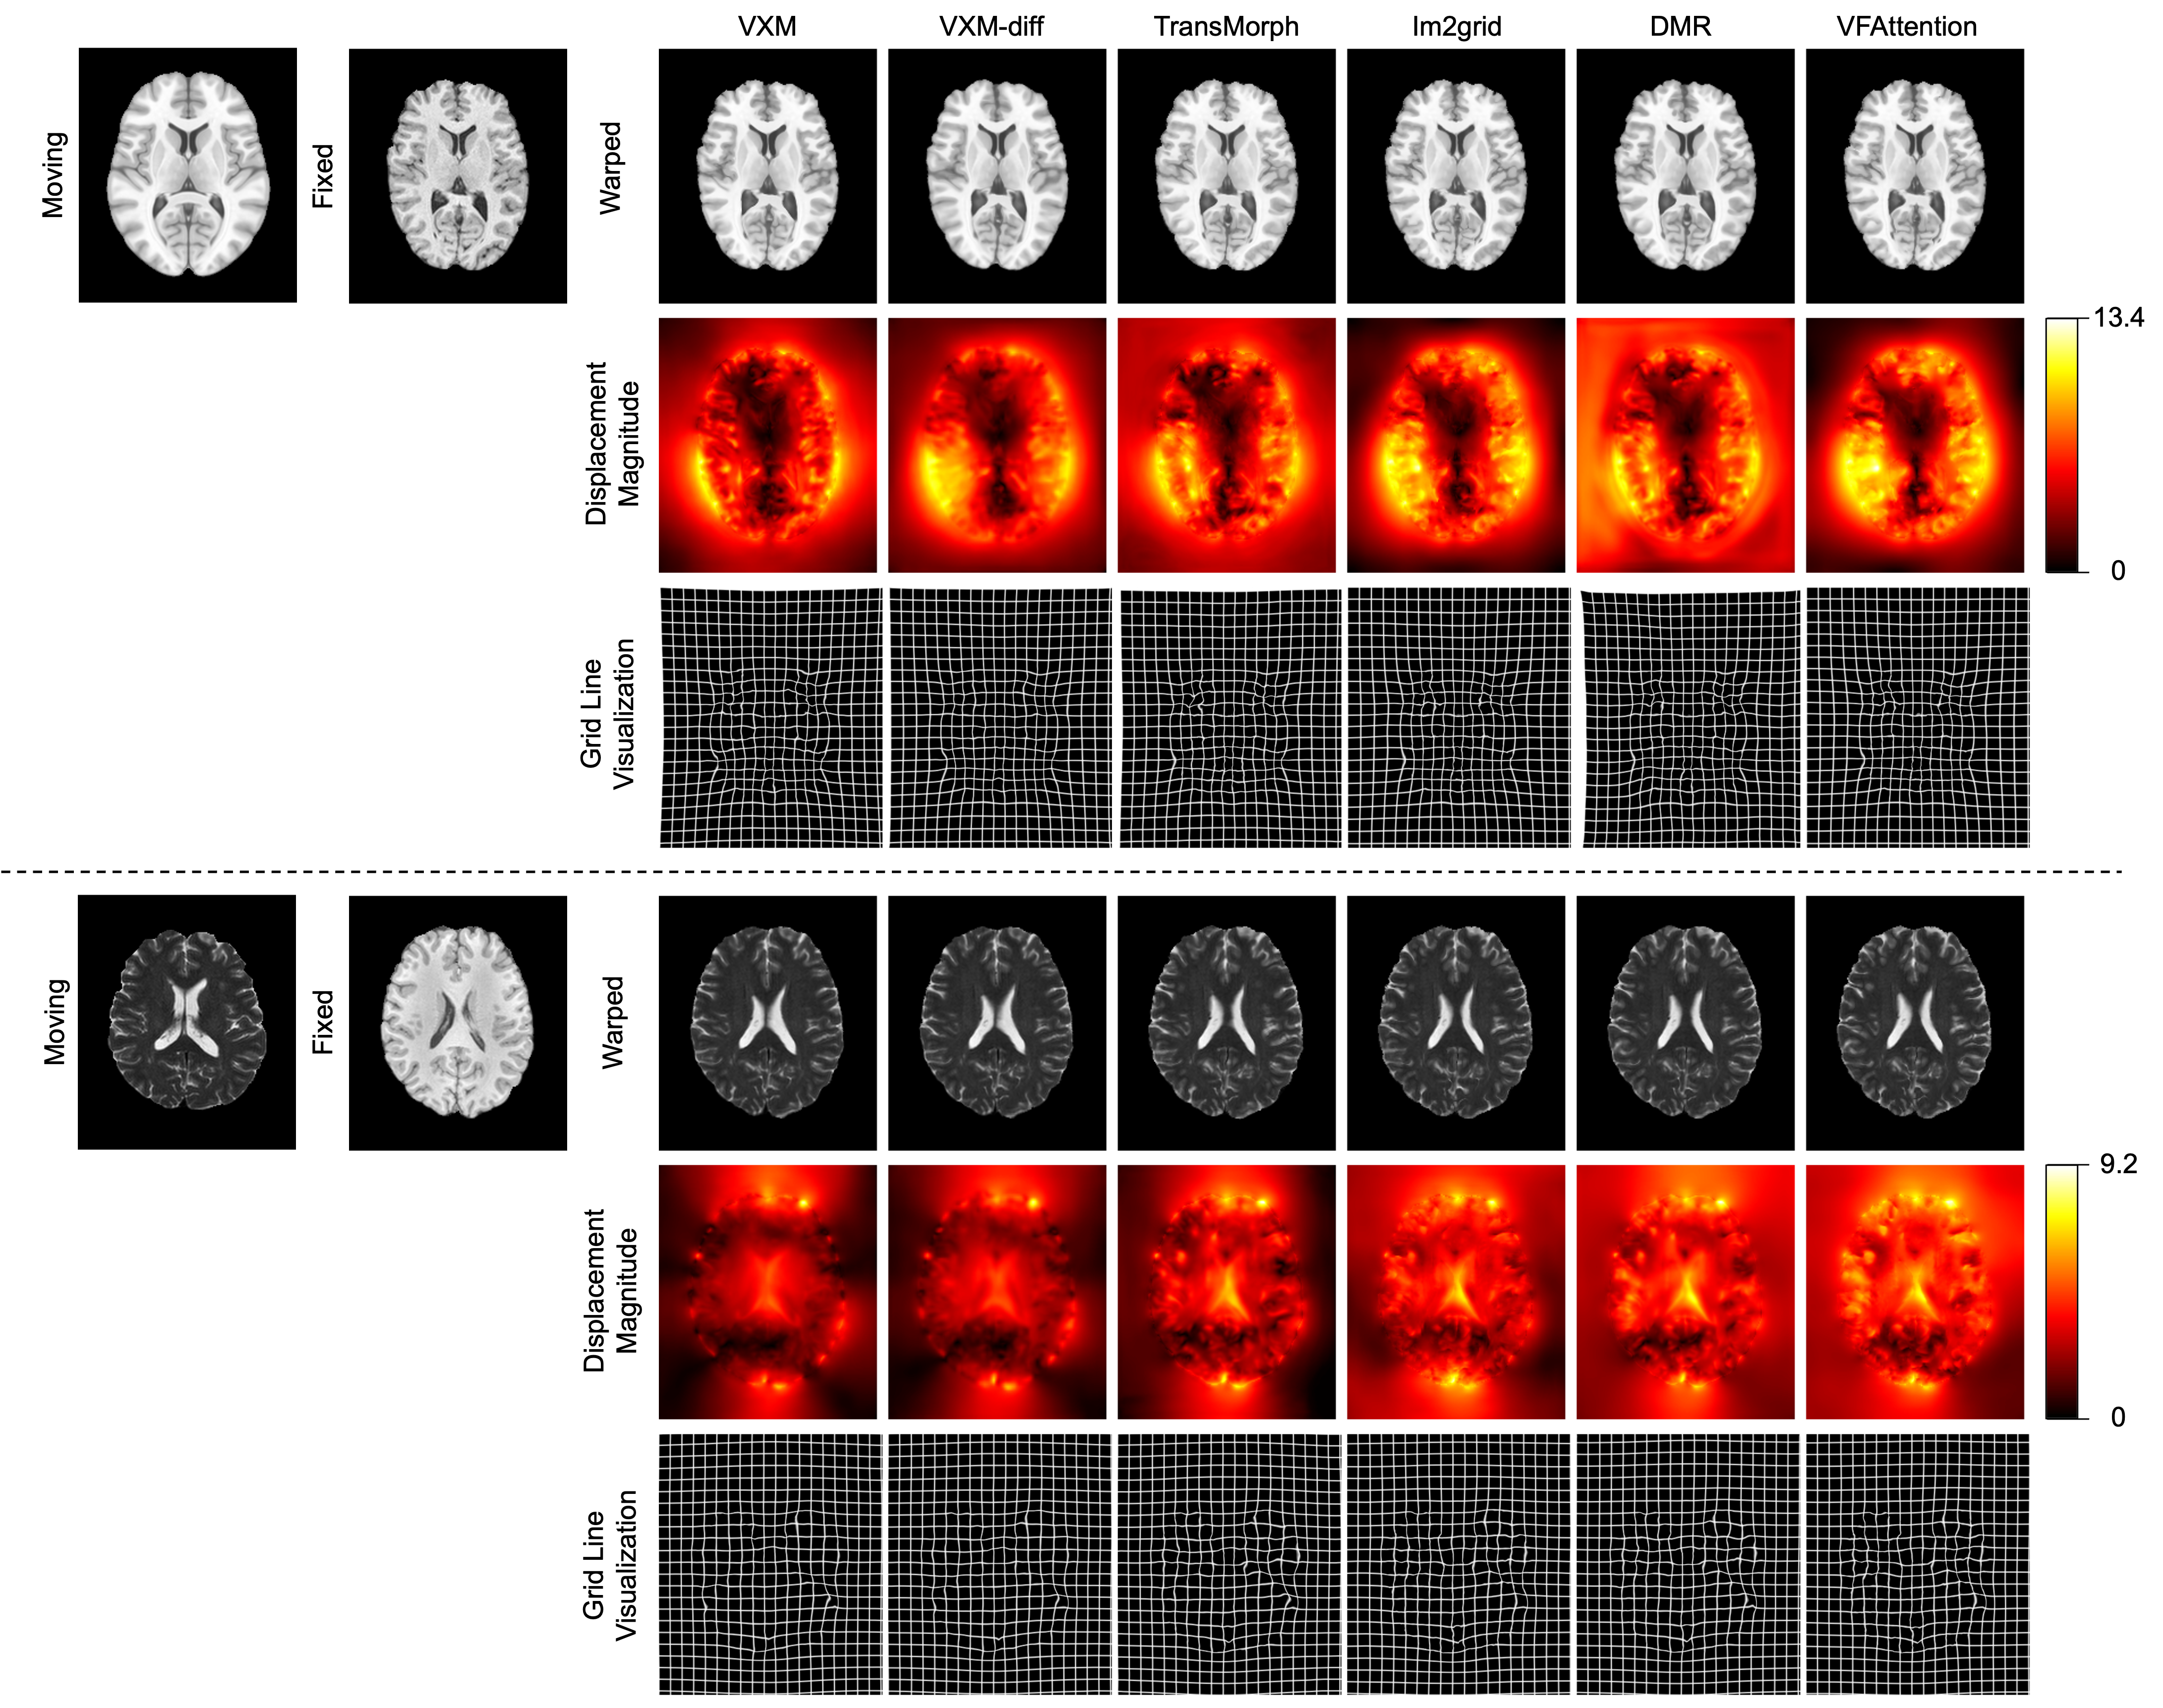

Baseline Methods. In the first two experiments, we compared VFA with several state-of-the-art deep learning methods including: 1) Voxelmorph (VXM) [7]: A deep learning method based on a U-Net architecture; 2) Voxelmorph-diff (VXM-diff) [41]: A variant of VoxelMorph with a scaling-and-squaring layer to encourage diffeomorphic registration; 3) TransMorph [8]: A hybrid deep learning architecture that combines the Transformer structure with convolutional networks; 4) Im2grid [12]: our previous method using coordinate translator modules; 5) DMR [27]: A deep learning based architecture based on the Deformer module; and 6) PR-Net++ [34]: A deep learning method that adopts a dual-stream architecture and incorporates correlation layers. We did not include traditional registration methods in our experiments since the selected comparison methods have demonstrated superior performance over traditional methods in previous studies.

Results. The performance of all the algorithms are summarized in Table 1 (left). VFA achieved the highest DSC among all algorithms with statistical significance (). We also report the effect size, calculated between the proposed method VFA and the comparison method with the highest mean DSC (Im2grid). The result further reinforces the superiority of VFA. Specifically, the Rank-Biserial Correlation (RBC) [46] was found to be , indicating a perfect positive relationship in the differences between paired observations. Additionally, the Common Language Effect Size (CLES) [47] was found to be , suggesting that there is a chance that a randomly selected pair will exhibit a difference in the expected direction favoring VFA. We also observed that VFA produced fewer folded voxels and smaller folded volumes compared with VXM, TransMorph, DMR, and PR-Net++ under the same choice of regularization weights . This behavior is likely related to the local search strategy adopted in the feature matching step, as evidenced by the similar results produced by Im2grid, which utilized a similar strategy. In contrast, TransMorph and DMR, which employed self-attention over a large window, did not exhibit this property. The smoothness of the displacement fields produced by each algorithm can be observed in Fig. 5. We also implemented a variant of VFA (VFA-Diff) with the addition of the scaling-and-scaling-technique. Both VXM-diff and VFA-diff demonstrated reduced folding compared to their original versions. We note that the scaling and squaring layer can be incorporated in all the algorithms shown in Table 1, although it cannot guarantee a perfect diffeomorphism due to the finite difference approximation of the Jacobian computation [39].

Results. The performance of all the algorithms are summarized in Table 1 (right). Since inter-modality registration is a more challenging task than intra-modality registration, there is a decrease in registration accuracy for all algorithms. Nevertheless, VFA achieved the highest DSC among all algorithms with statistical significance (). We also report the effect size, calculated between the proposed method VFA and the comparison method with the highest mean DSC (DMR). The Rank-Biserial Correlation (RBC) [46] was found to be and the Common Language Effect Size (CLES) [47] was found to be . Sample results are shown in Fig. 5.